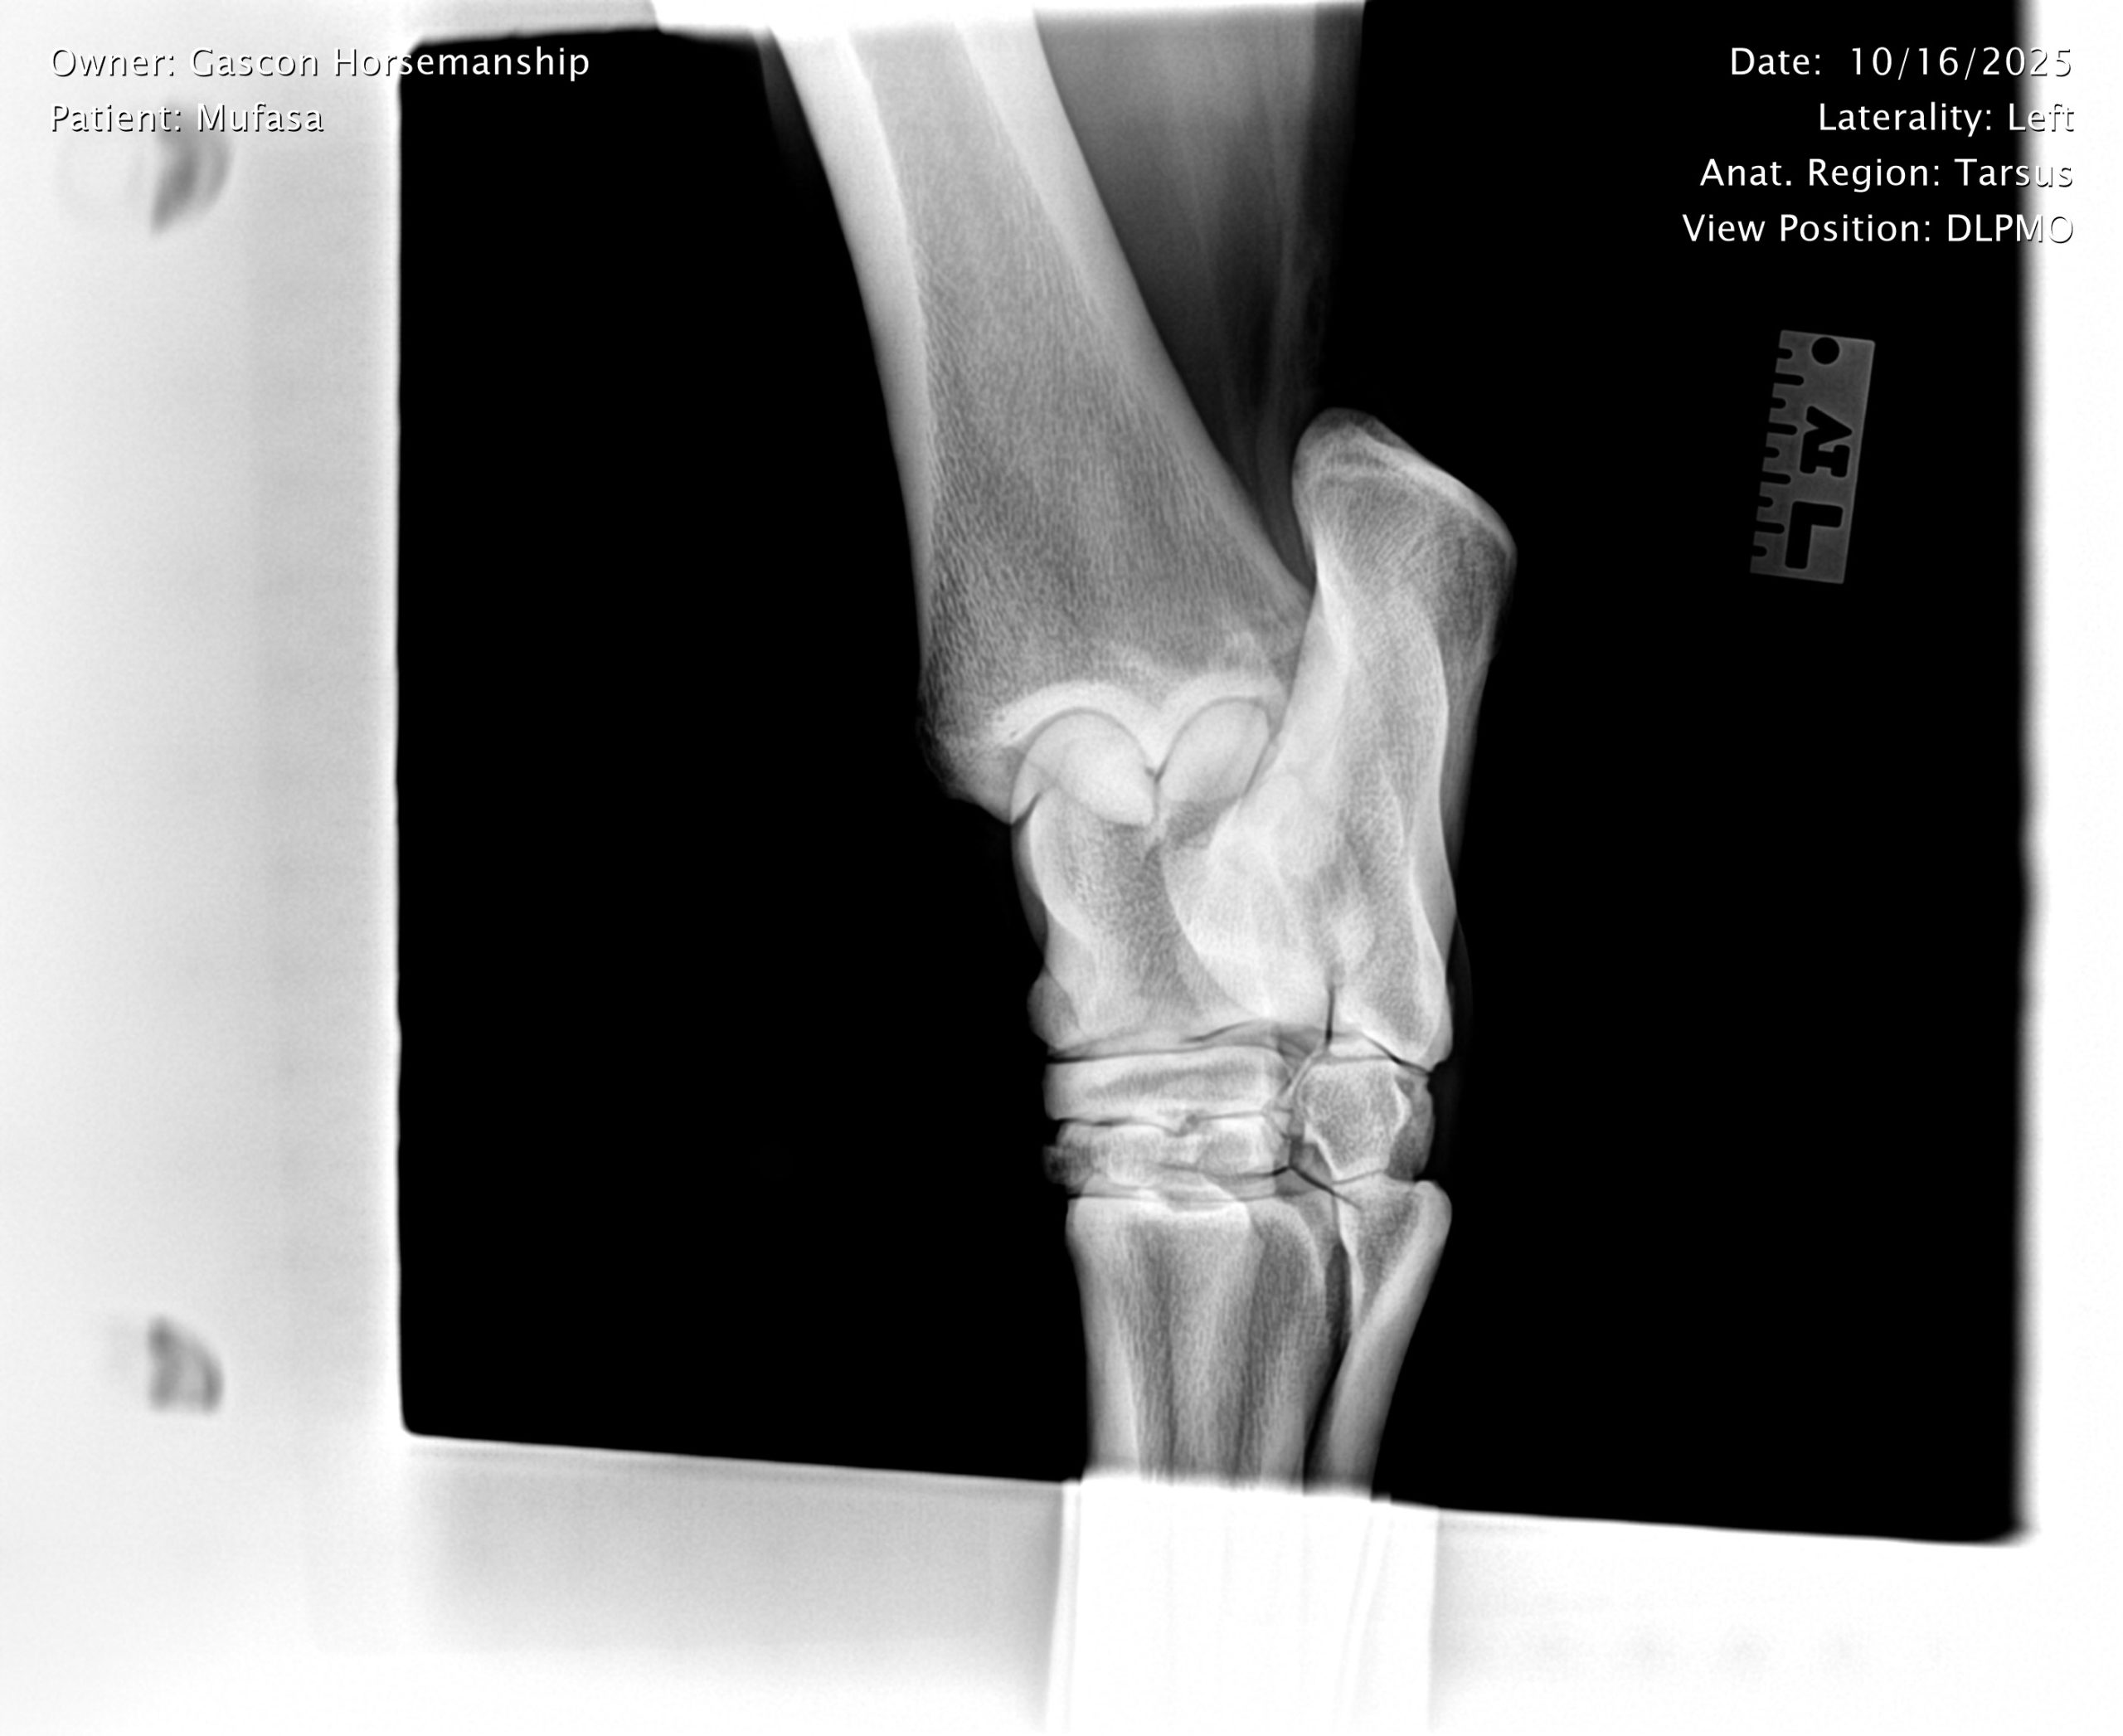

He already has a full pre-purchase exam on file, complete with 25 X-rays included in his album.